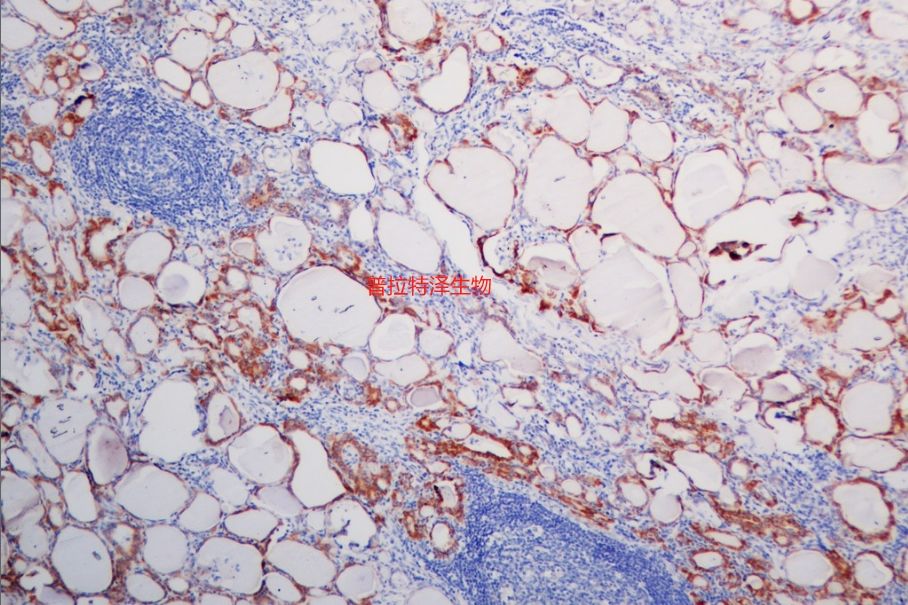

原位雜交是一種在細胞或組織水平上檢測特定核酸序列的技術(shù)。然而,在實際應(yīng)用中,原位雜交實驗常常會遇到一些問題,如非特異性染色、背景信號過高、假陽性或假陰性結(jié)果等。普拉特澤生物承接原位雜交等病理染色相關(guān)服務(wù)上萬例,積累了操作大量經(jīng)驗,為大家詳細分享原位雜交常見問題的分析與對策,同時為廣大科研工作者開展線上的理論培訓(xùn)與線下實操,可承接染色實驗外包服務(wù)。